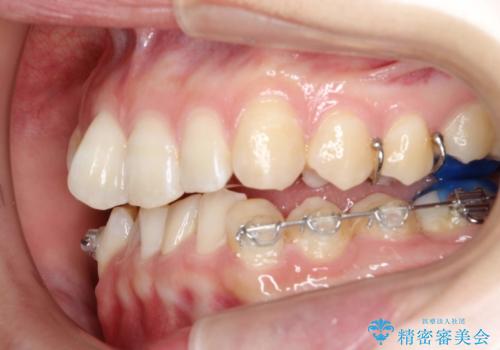

ハーフリンガル ワイヤー矯正による非抜歯・過蓋咬合の治療

- 非抜歯、大臼歯遠心移動による臼歯関係の是正・過蓋の改善をハーフリンガル・ワイヤー矯正にて計画した。

しかし、諸々の理由でマウスピース矯正をおこなえない場合、本例のようにワイヤーを用いて治療することも可能ですが、そもそも装置が歯につかないため、非常に大変な労力を費やすことになります。